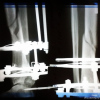

Аппарат ИлизароваЭто сегодняшние.

Голеностоп снимать не стала, сняла именно берцовую

Аппарат ИлизароваКартина вообще то не очень понятная.. снимки должны захватывать ДВА сустава, в твоем случае коленный и голеностопный суставы. Мы не профи конечно и профи не увидит по данным снимкам правильную длину, ось и ротацию.. Как по мне, то кажется на первый взгляд, щель между отломками не маленькая.. Я всем советовал, создайте темку на сайте врачей, ответят на все вопросы! Здесь мы общаемся над различными вопросами и советами из своего опыта.. там ответят конкретно, хорошо или что то надо менять, ух уж эти аппараты.. их ставят либо временно, либо в крайнем по показаниям случае. Дам еще раз ссылку, что бы не искать, раздел травматологии там есть и читайте правила подачи, ссылку на мою тему я давал сюда.

Аппарат ИлизароваДа я понимаю, что снимки выложила не ахти. Просто снимок большого формата у нас делают. Он мне банально не помещается на стекле.

А сустав снимок захватывает только один-голеностоп.

На всех снимках.

А щель понятно дело еще имеется. у меня всего два месяца, в лучшем случае это только половина срока.

И врач так сказал-для двух месяцев хорошо, но понятное дело что это еще не конец.

Аппарат ИлизароваНа окне не надо фотографировать.... я же писал как лучше и на форуме там в правилах найдете как нужно. На монитор не влезает если, то подключи вместо монитора телевизор (если есть конечно и подключается к нему комп или ноут) Ну на фоне окна лишний пейзаж в виде домов и деревьев.. фон дает не нужный. А у меня вот эти щели за год ни как... и не половина срока, потому что идеально это минимум 6 месяцев в аппарате. И не надо пробовать, а скорее нужно..